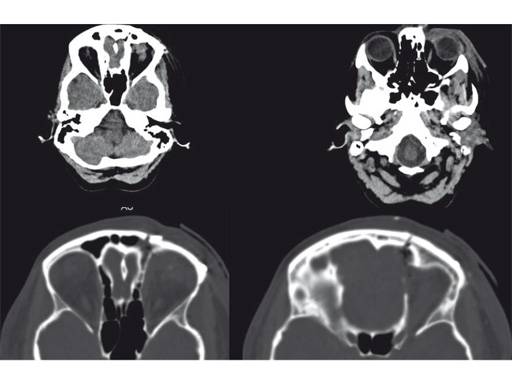

Resection of orbital lymphangioma in a 29-year-old woman.

Case provided by Christian Matula, Wien, Austria

Fig 1 Preoperative images.